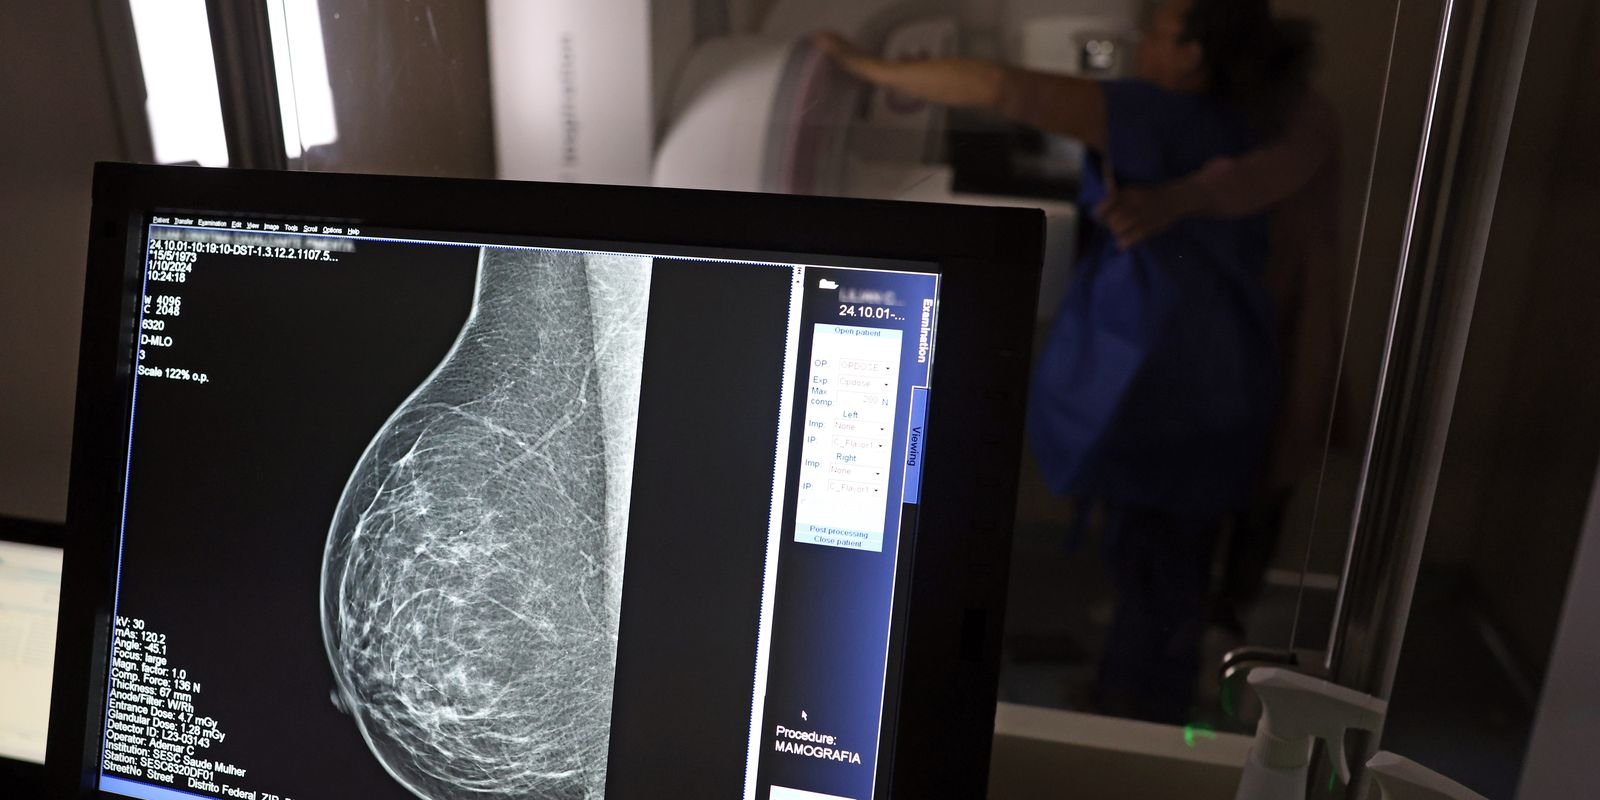

O Ministério da Saúde passou a recomendar o acesso a mamografia, via Sistema Único de Saúde (SUS), para mulheres de 40 a 49 anos – mesmo que não haja sinais ou sintomas de câncer de mama. De acordo com a pasta, a faixa etária concentra 23% dos casos da doença, e a detecção precoce aumenta as chances de cura.

Até então, a orientação era que o exame fosse feito a partir dos 50 anos.

As mamografias via SUS em pacientes com menos de 50 anos, de acordo com a pasta, representam 30% do total, o equivalente a mais de 1 milhão apenas no ano de 2024.

Outra medida anunciada é a ampliação da faixa etária para o rastreamento ativo – quando a mamografia é solicitada de forma preventiva a cada dois anos. A idade limite, até então, era 69 anos. Agora, passa a ser 74 anos. Dados do ministério revelam que quase 60% dos casos de câncer de mama estão concentrados entre 50 e 74 anos.

Os números mostram que, em 2024, cerca de 4 milhões de mamografias para rastreamento e 376,7 mil exames diagnósticos foram realizados no SUS.